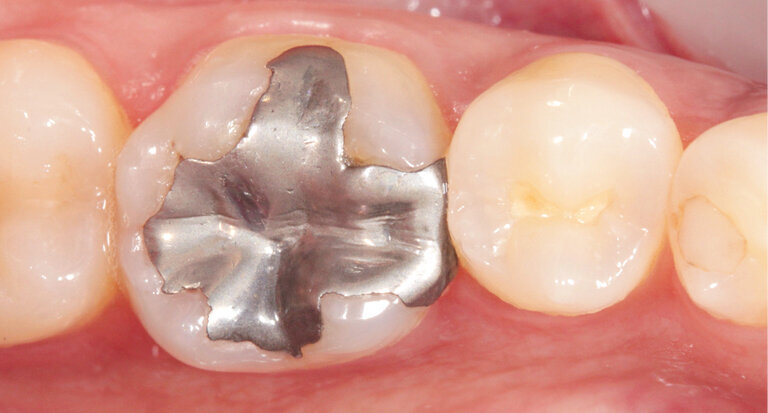

The pre-op showed a defective amalgam filling on tooth 36 in the lower posterior region. The filling needed replacing (Fig. 1). The indication for a multi-surface inlay was given.

Fig. 1: Preoperative situation: defective amalgam filling on tooth 36

Shade selection is performed on the natural dentition, primarily on the neighbouring teeth. We decided to use shade HT A2. The HT blocks are a good choice, particularly when it comes to producing fairly small restorations such as inlays as they provide a pronounced chameleon effect. Once the old amalgam was removed, the tooth was prepared in line with the recommended preparation guidelines (Fig. 2). Then, an optical impression was taken using an intraoral scanner and the inlay was designed in the CAD module (Fig. 3). Subsequently, the restoration was ground from the block.